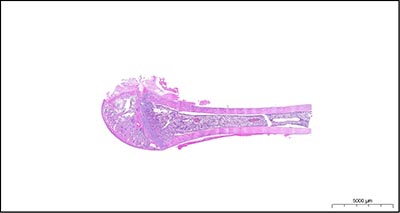

骨组织脱钙标准技术流程:

1.组织选择:脱钙前选择适当骨组织,锯成薄片,厚度2~5mm。

2.固定:常温下固定4~6小时,固定液体积要大于标本体积20~30倍。固定液最好选用可保存欲显示的组织成分的相应固定剂。

3.脱钙:将已固定的骨块置于已选好的脱钙液内进行脱钙,严格控制时间,及时更换新液。

4.酸的中和:保护骨组织不过度膨胀,不影响染色质量。

5.充分水洗:去酸,为以后脱水、透明、埋蜡打下基础。